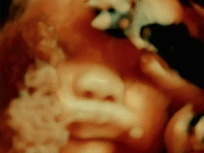

Um documentário que celebra os cinco séculos que separam a atualidade de um feito do anatomista André Vésale.